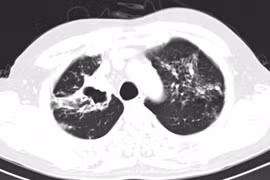

Nhiễm trùng phổi do nontuberculous mycobacteria (NTM) xuất hiện ở nhiều nơi trên thế giới. Bệnh phổi NTM tương tự lao, nhiễm trùng da và mô mềm, nhiễm trùng hệ thần kinh trung ương, nhiễm khuẩn huyết, nhiễm trùng mắt và các bệnh nhiễm trùng khác...